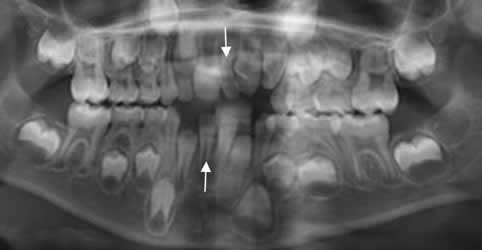

Fig 82. Mesiodens.

Ortopantografía. Dientes supernumerarios hipoplásicos, superiores e inferiores entre los incisivos, por mesiodens.